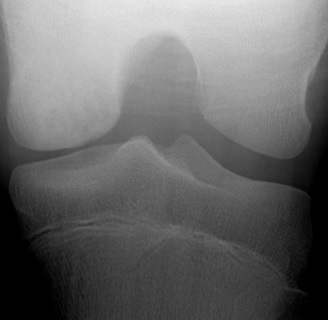

[Figure caption and citation for the preceding image starts]: Healed osteochondritis dissecansFrom the collection of H. Chambers, MD [Citation ends].